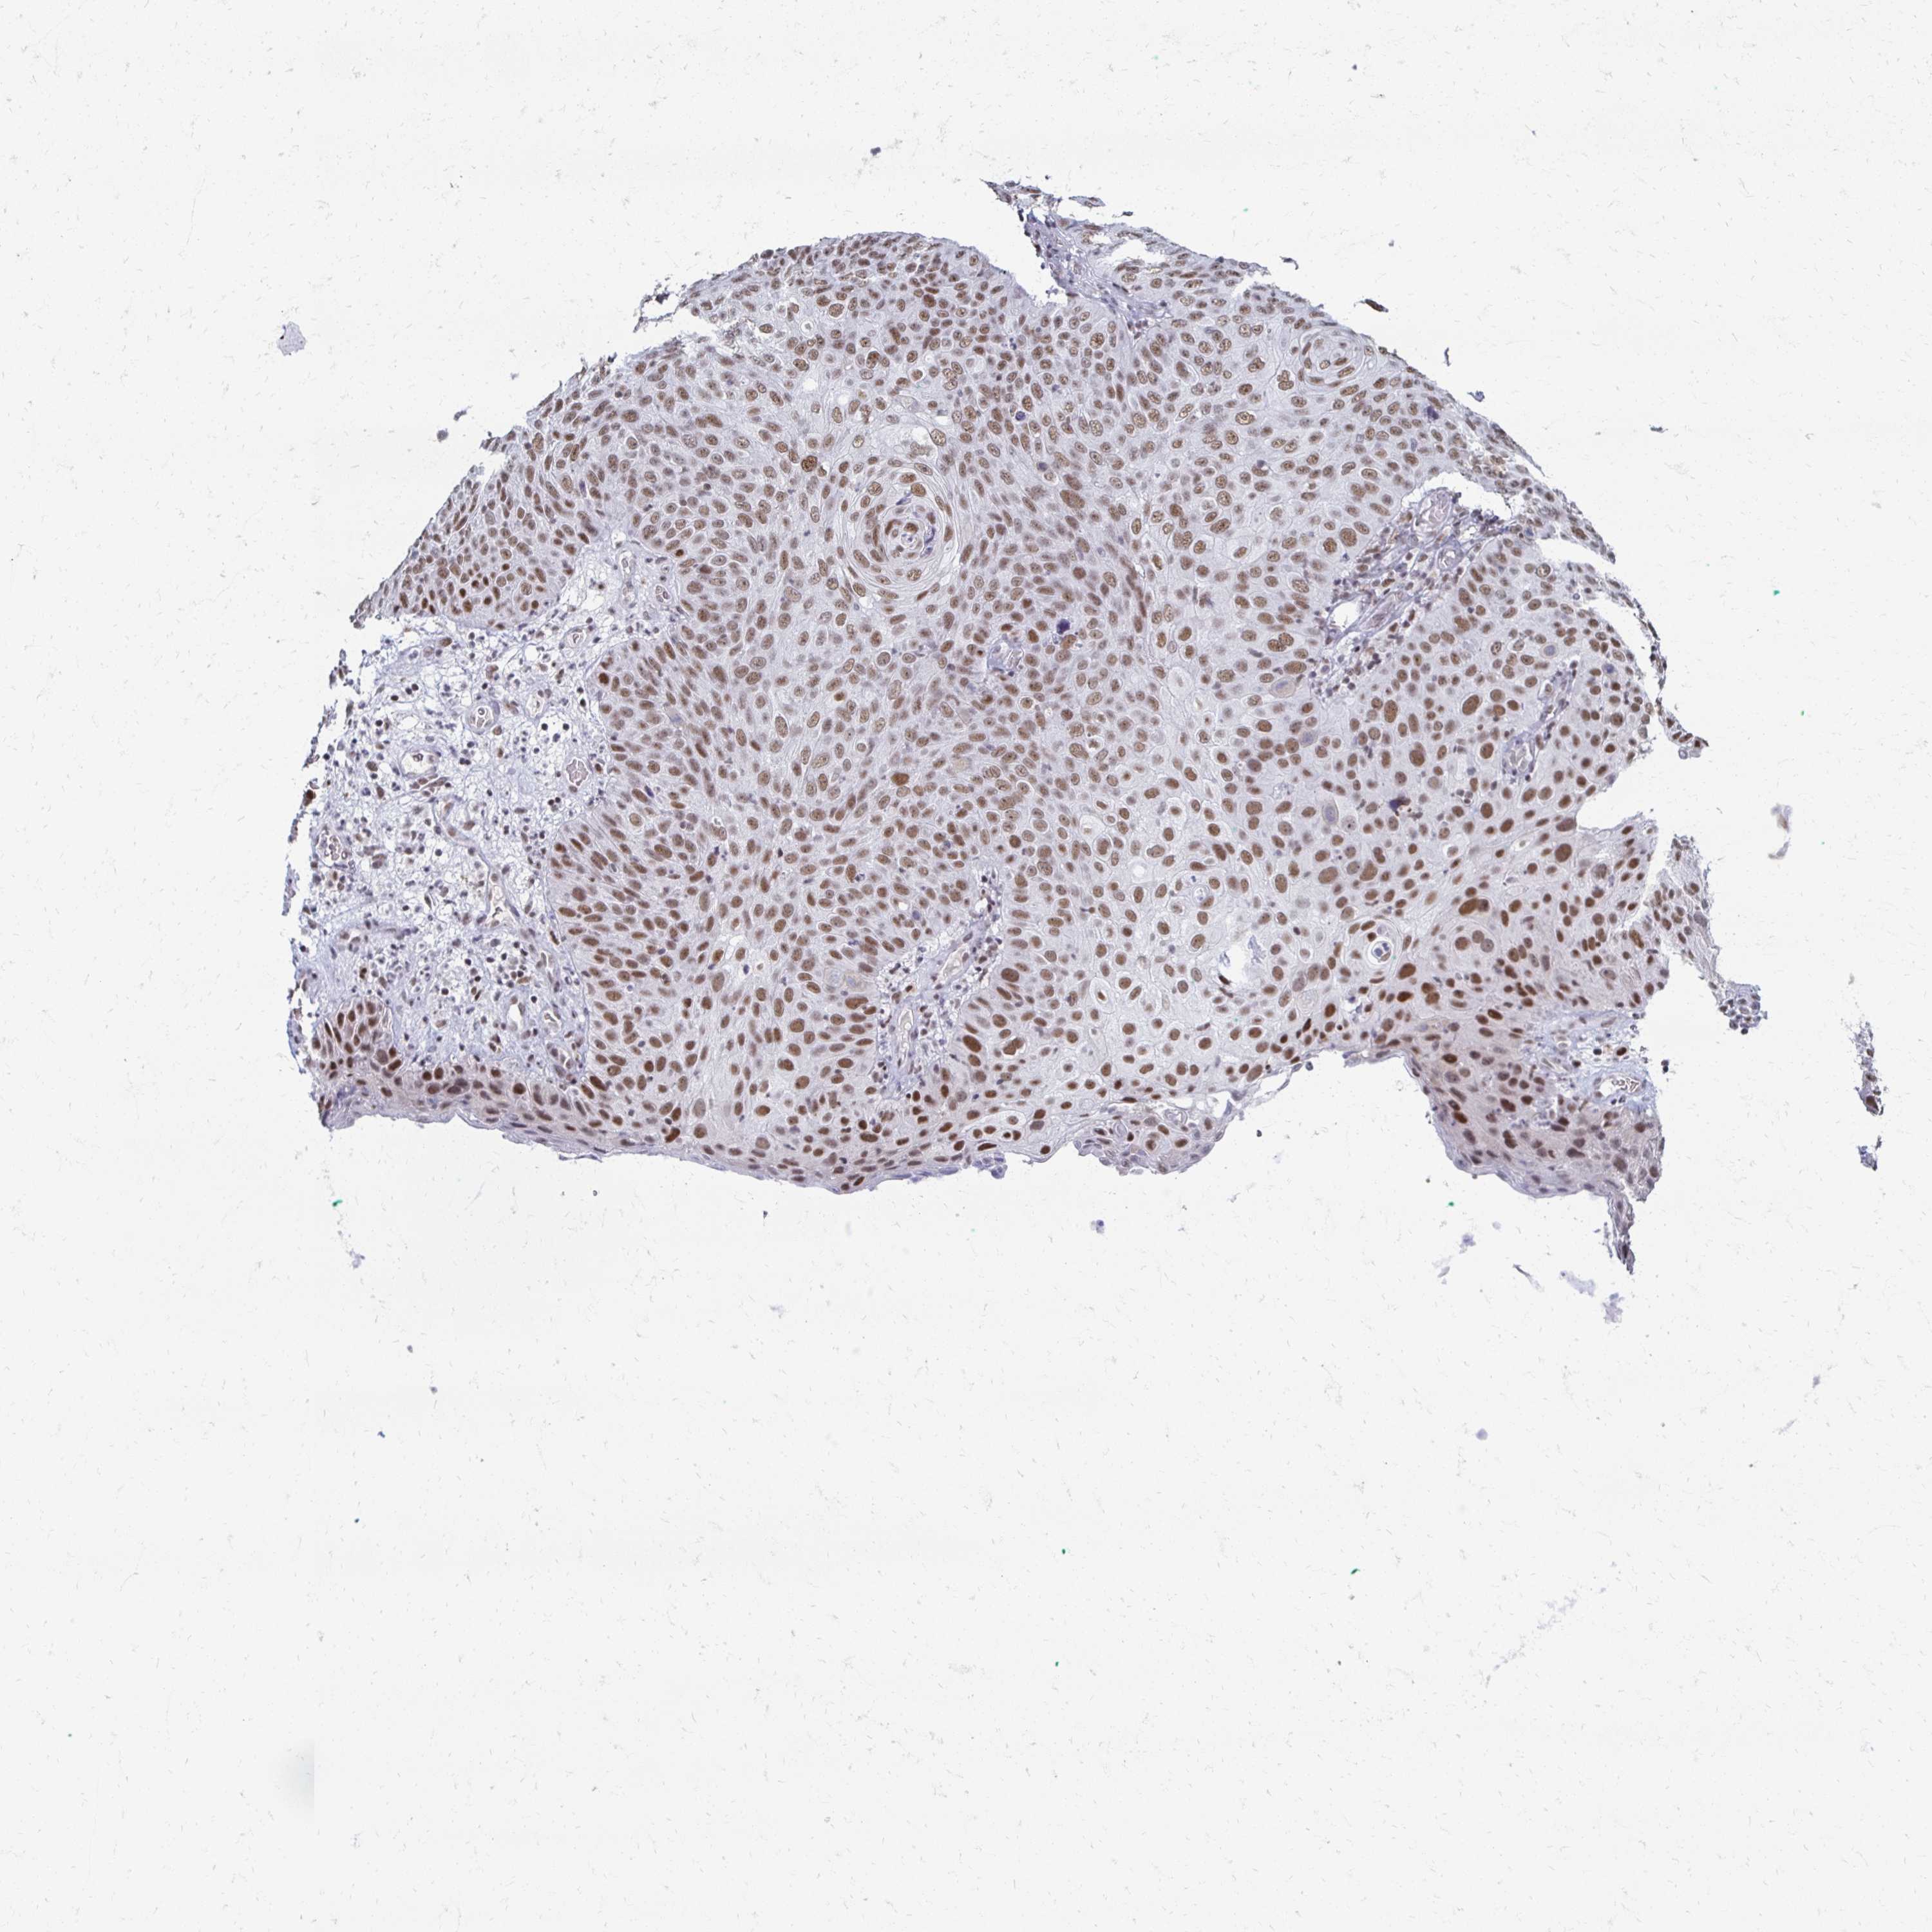

SKIN CANCER - Protein expressioni

A mouse-over function shows sample information and annotation data. Click on an image to view it in a full screen mode. Samples can be filtered based on level of antibody staining by selecting one or several of the following categories: high, medium, low and not detected. The assay and annotation is described here.

Antibody stainingi

Antibody staining in the annotated cell types in the current human tissue is reported as not detected, low, medium, or high, based on conventional immunohistochemistry profiling in selected tissues. This score is based on the combination of the staining intensity and fraction of stained cells.

Each image is clickable and will lead to virtual microscopy that enables deeper exploration of all samples and also displays staining intensity scores, fraction scores and subcellular localization as well as patient and tissue information for each sample.

Antibody HPA052757

Basal cell carcinoma